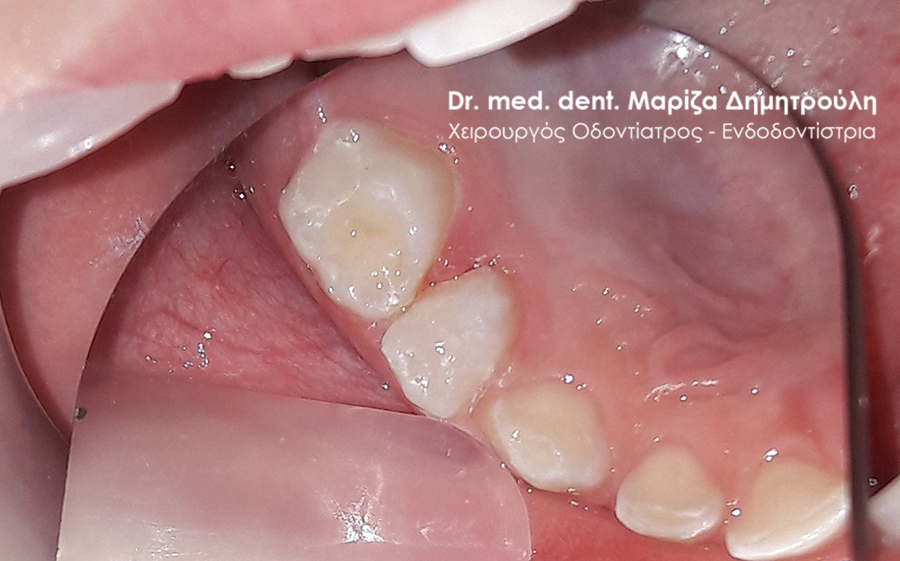

Κορίτσι ηλικίας 9 ετών αναφέρει οτι πονάει στην πάνω αριστερή πλευρά του στόματος της όταν μασάει. Μετά την κλινική εξέταση διαπιστώθηκε η ύπαρξη 2 τερηδονισμένων δοντιών. Στον πρώτο μόνιμο αριστερό γομφίο είναι εμφανής η ύπαρξη τερηδόνας, της οποίας η έκταση αποδείχτηκε αρκετά βαθιά κατά τη διάνοιξη του δοντιού. Στο δεύτερο νεογιλό (παιδικό) γομφίο παρατηρήθηκε η ύπαρξη τερηδονικής κοιλότητας μεσαίου βάθους.

Μετά την απομάκρυνση της τερηδόνας από τα δύο δοντάκια πραγματοποιήθηκαν λευκά σφραγίσματα σύνθετης ρητίνης.

ΠΡΙΝ

ΜΕΤΑ